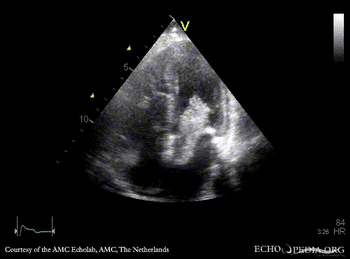

Giant myxoma in left atrium

PSAX